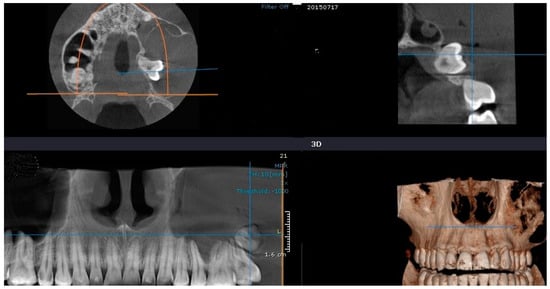

- Allison, J.R.; Garlington, G. The value of cone beam computed tomography in the management of dentigerous cysts—A review and case report. Dent. Update 2017, 44, 182–188. [Google Scholar] [CrossRef] [PubMed][Green Version]

- Erdelyi, R.-A.; Duma, V.-F.; Sinescu, C.; Dobre, G.M.; Bradu, A.; Podoleanu, A. Dental diagnosis and treatment assessments: Between X-rays radiography and optical coherence tomography. Materials 2020, 13, 4825. [Google Scholar] [CrossRef]

- Erdelyi, R.-A.; Duma, V.-F.; Sinescu, C.; Dobre, G.M.; Bradu, A.; Podoleanu, A. Optimization of X-ray investigations in dentistry using optical coherence tomography. Sensors 2021, 21, 4554. [Google Scholar] [CrossRef]

| 2 | 11 y/o | M | Maxilla | 1.5 (right maxillary second premolar) | yes | 4.52 |